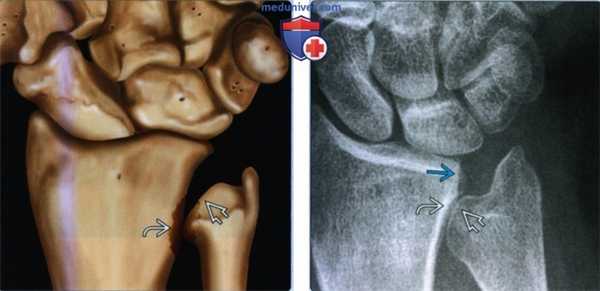

(Слева) На фронтальном рисунке показаны повреждения, характерные для синдрома сдавливания крючковидной и полулунной костей. Полулунная кость имеет крючковидную (медиальную) суставную поверхность, которая сочленяется прямо с крючковидной костью. Хрящ проксимальной поверхности крючковидной кости отсутствует на всю толщину и образуется субхондральная киста.

(Справа) На фронтальной МРТ PDBИ FS определяется II тип полулунной кости с длиной крючковидной суставной поверхности 5 мм. Суставной хрящ дистальной поверхности полулунной кости и проксимальной поверхности крючковидной кости истончен с реактивным субхондральным отеком костного мозга в крючковидной кости.